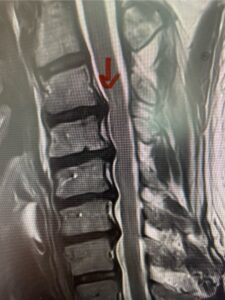

Another patient, a 77 year-old female, presents with pain, numbness, and weakness of her arms and difficulty with balance over a 6-month period. MRI revealed severe osteophytic disease at C5-C7 with cord compression (Fig. 4). Further work-up by fine-cut cervical CT to evaluate the nature of compression revealed a completely calcified osteophyte (Fig. 5). Although the patient had a good lordosis and a posterior cervical approach would accomplish an adequate decompression, we elected to perform a two-level anterior cervical discectomy and fusion. This particular osteophyte is formidable because of its size but the compression was all anterior and would be a less invasive approach. Fortunately, during the procedure, the patient had a fair amount of osteoporosis which allowed the osteophyte to be drilled and bit away with considerable ease. Interestingly, the C6 7 osteophyte which was more a sheet of osteophyte was more challenging to remove. In the end the decompression went well, and we placed two interbody devices filled with bone graft with plates at each level (Fig. 6). The patient had a nice recovery with immediate reduction of pain and numbness. This case demonstrates the importance of recognition of cervical myelopathy in its early stages. A significant reversal of function is generally the rule if the patient has appropriate correlative findings on exam and MRI, particularly with long tract distribution weakness development within a year time period.

Figs 4a: Sagittal and axial T2-weighted cervical MRIs demonstrating large osteophyte worse at C5-6 compressing spinal cord more eccentrically to the left (red arrows)

Fig 4b

Fig 4c